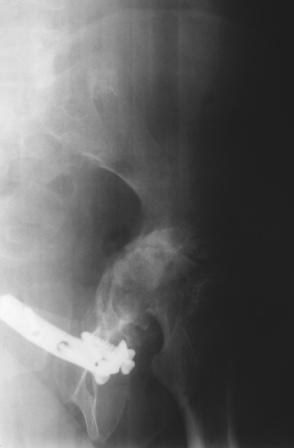

Уважаемые коллеги! Пациентка 32 года с застарелым повреждением таза, после остеосинеза лонного сочленения пластиной. Посоветуйте с выбором тактики и методик лечения.

Получила травму в феврале 2004г в г.Лобытнанги ЯНАО Тюм.обл. Через неделю после поступления выполнен остеосинтез лонного сочленения пластиной. 1,5 месяца на скелетном вытяжении. В последующем ходит при помощи костылей с нагрузкой на правую ногу. Имеется нестабильность половин таза, неправильно-консолидированный перелом левой вертлужной впадины, невропатия седалищного нерва слева. В результате невропатии седалищного нерва сформировалась эквинусная установка левой стопы,парестезии по подошвенной поверхности.

Направлена к нам для устранения патологической установки стопы и эндопротезирования левого тазобедренного сустава, также имеется миграция шурупов пластины, фиксирующей лонное сочленение.

Клинически: ходит на костылях с нагрузкой на правую ногу. Левая стопа в эквинусе. Осевая нагрузка на левую н\конечность болезненна в области левого тазобедренного сустава, при прикосновениях к подошвенной поверхности стопы у пациентки чувство зжения. В левом коленном суставе полный обьем движений, в левом тазобедренном резко ограничено отведение и ротация, укорочение левой н\конечности на 2,5 см. При полипроекционной и функциональной Р-графии выявлена нестабильность левого КПС и лонного сочленения, консолидированный в порочном положении поперечный оскольчатый перелом левой вертлужной впадины с центральным смещением головки бедра. Нами выполнена коррекция деформации левой стопы. Планируется выполнить введение 2 канюлированных илиосакральных винтов слева, реостеосинтез лонного сочленения реконструктивной пластиной, после заживления ран - тотальное эндопротезирование левого тазобедренного сустава.